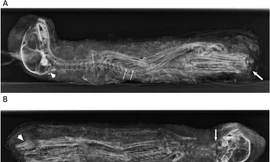

Một nghiên cứu mới cho thấy, từ hai ngàn năm trước, người Ai Cập đã mua xác ướp mèo từ người nuôi gia súc để để làm vật hiến sinh tế lễ cho các nữ thần Bastet.